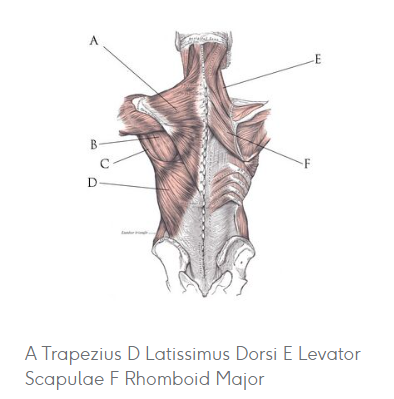

[Anatomy] Back muscle(등근육)

1. Superficial Group |

Scapula movement - Trapezius (승모근) - Latissimus Dorsi (광배근) - Levator Scapulae (견갑거근) - Rhomboid major (대능형근) - Rhomboid minor (소능형근) |